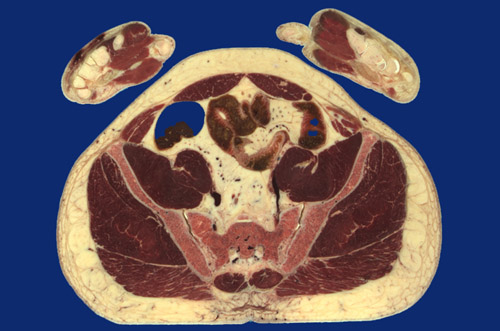

Identify the following regions in the image above: Rectus abdominis - External oblique - Internal oblique - Psoas major - Iliacus - Gluteus minimus - Gluteus medius - Gluteus maximus - Transversospinalis m. pars multifidus) - Ilium - Sacrum - Sacroiliac joint - Cecum - Ileum